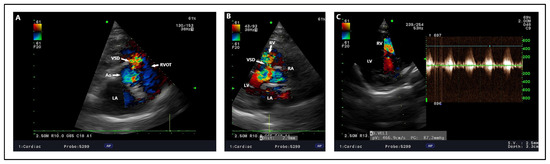

4.2. Echocardiography, Radiography, ECG Findings

- Kim, Y.; Kwon, D.; Kim, S.S.; Lee, K.; Yoon, H. Echocardiographic Changes in the Progress of Reverse Shunt and Improvement to Left-to-Right Shunt after Medical Treatment in Dogs with Bidirectional Patent Ductus Arteriosus or Ventricular Septal Defect: A Report of Two Cases. Vet. Med. Sci. 2023, 9, 1044–1052. [Google Scholar] [CrossRef]